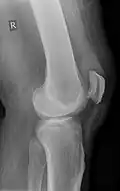

| An x-ray demonstrating quadriceps tendon rupture. Note the abnormal angle of the patella and soft-tissue swelling marked by the arrow. | |

Quadriceps tendon rupture in plain X-ray -